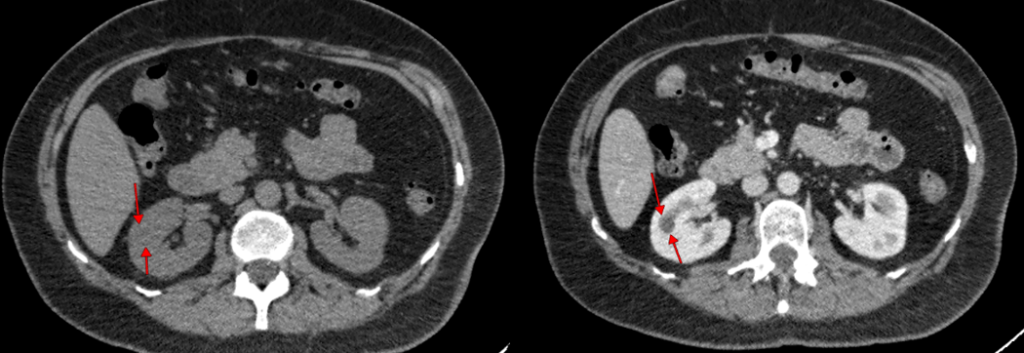

Мультиспиральная компьютерная томография (МСКТ) брюшной полости– является высокоинформативным методом диагностики, который позволяет визуализировать органы и ткани организма с высоким разрешением. Нашей особенностью является возможность проведения МСКТ с применением внутривенного контраста, что позволяет лучше дифференцировать границы нормальных и патологически измененных тканей.

Исследование показано при наличии подозрений на опухоль, увеличение лимфатических узлов, поражение печени, поджелудочной железы, селезенки и других органов. Оно помогает определить локализацию и размеры новообразования, оценить степень распространения болезни и выбрать оптимальную тактику лечения.